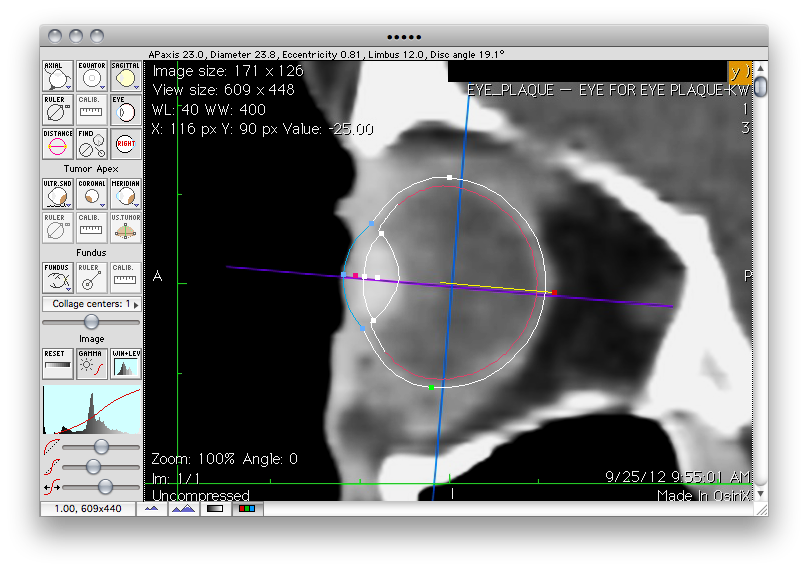

Assure that the axial image is being displayed and click the Eye button adjacent to the Calib. button to display the eye sizing tool.

• Turn off the Ruler tool. If you leave the ruler enabled it might overlap the eye in the image and interfere with your ability to interactively drag the eye sizing tool control points.

• Select left or right eye using the button just below the Eye button. The eye sizing tool orientation will adjust to the selected eye.

• Click in the middle of the eye sizing tool and drag the tool over the appropriate eye.

• Adjust the eye size to match the image by dragging the control markers. The dimensions of the eye are displayed in the status line just under the window title bar. You can enlarge the image in the vicinity of the eye using the "zoom" buttons at the lower left of the window.

• The red marker rotates the tool. The white and green markers control the diameter of the eye and lens position. The blue markers adjust the cornea & limbus. The magenta marker adjusts the ellipsoidal appearance of the anterior hemisphere of the model. The yellow lines of the tool represent an angle at the center of the PS model between the posterior pole of the eye and the center of the optic disk.

The 3D model in the setup window will change immediately in response to changes in the eye sizing tool so experiment with the tool's control handles to learn their properties. Place the Setup and Image windows side-by-side as you drag the eye sizing tool control handles to observe the behavior of the model.